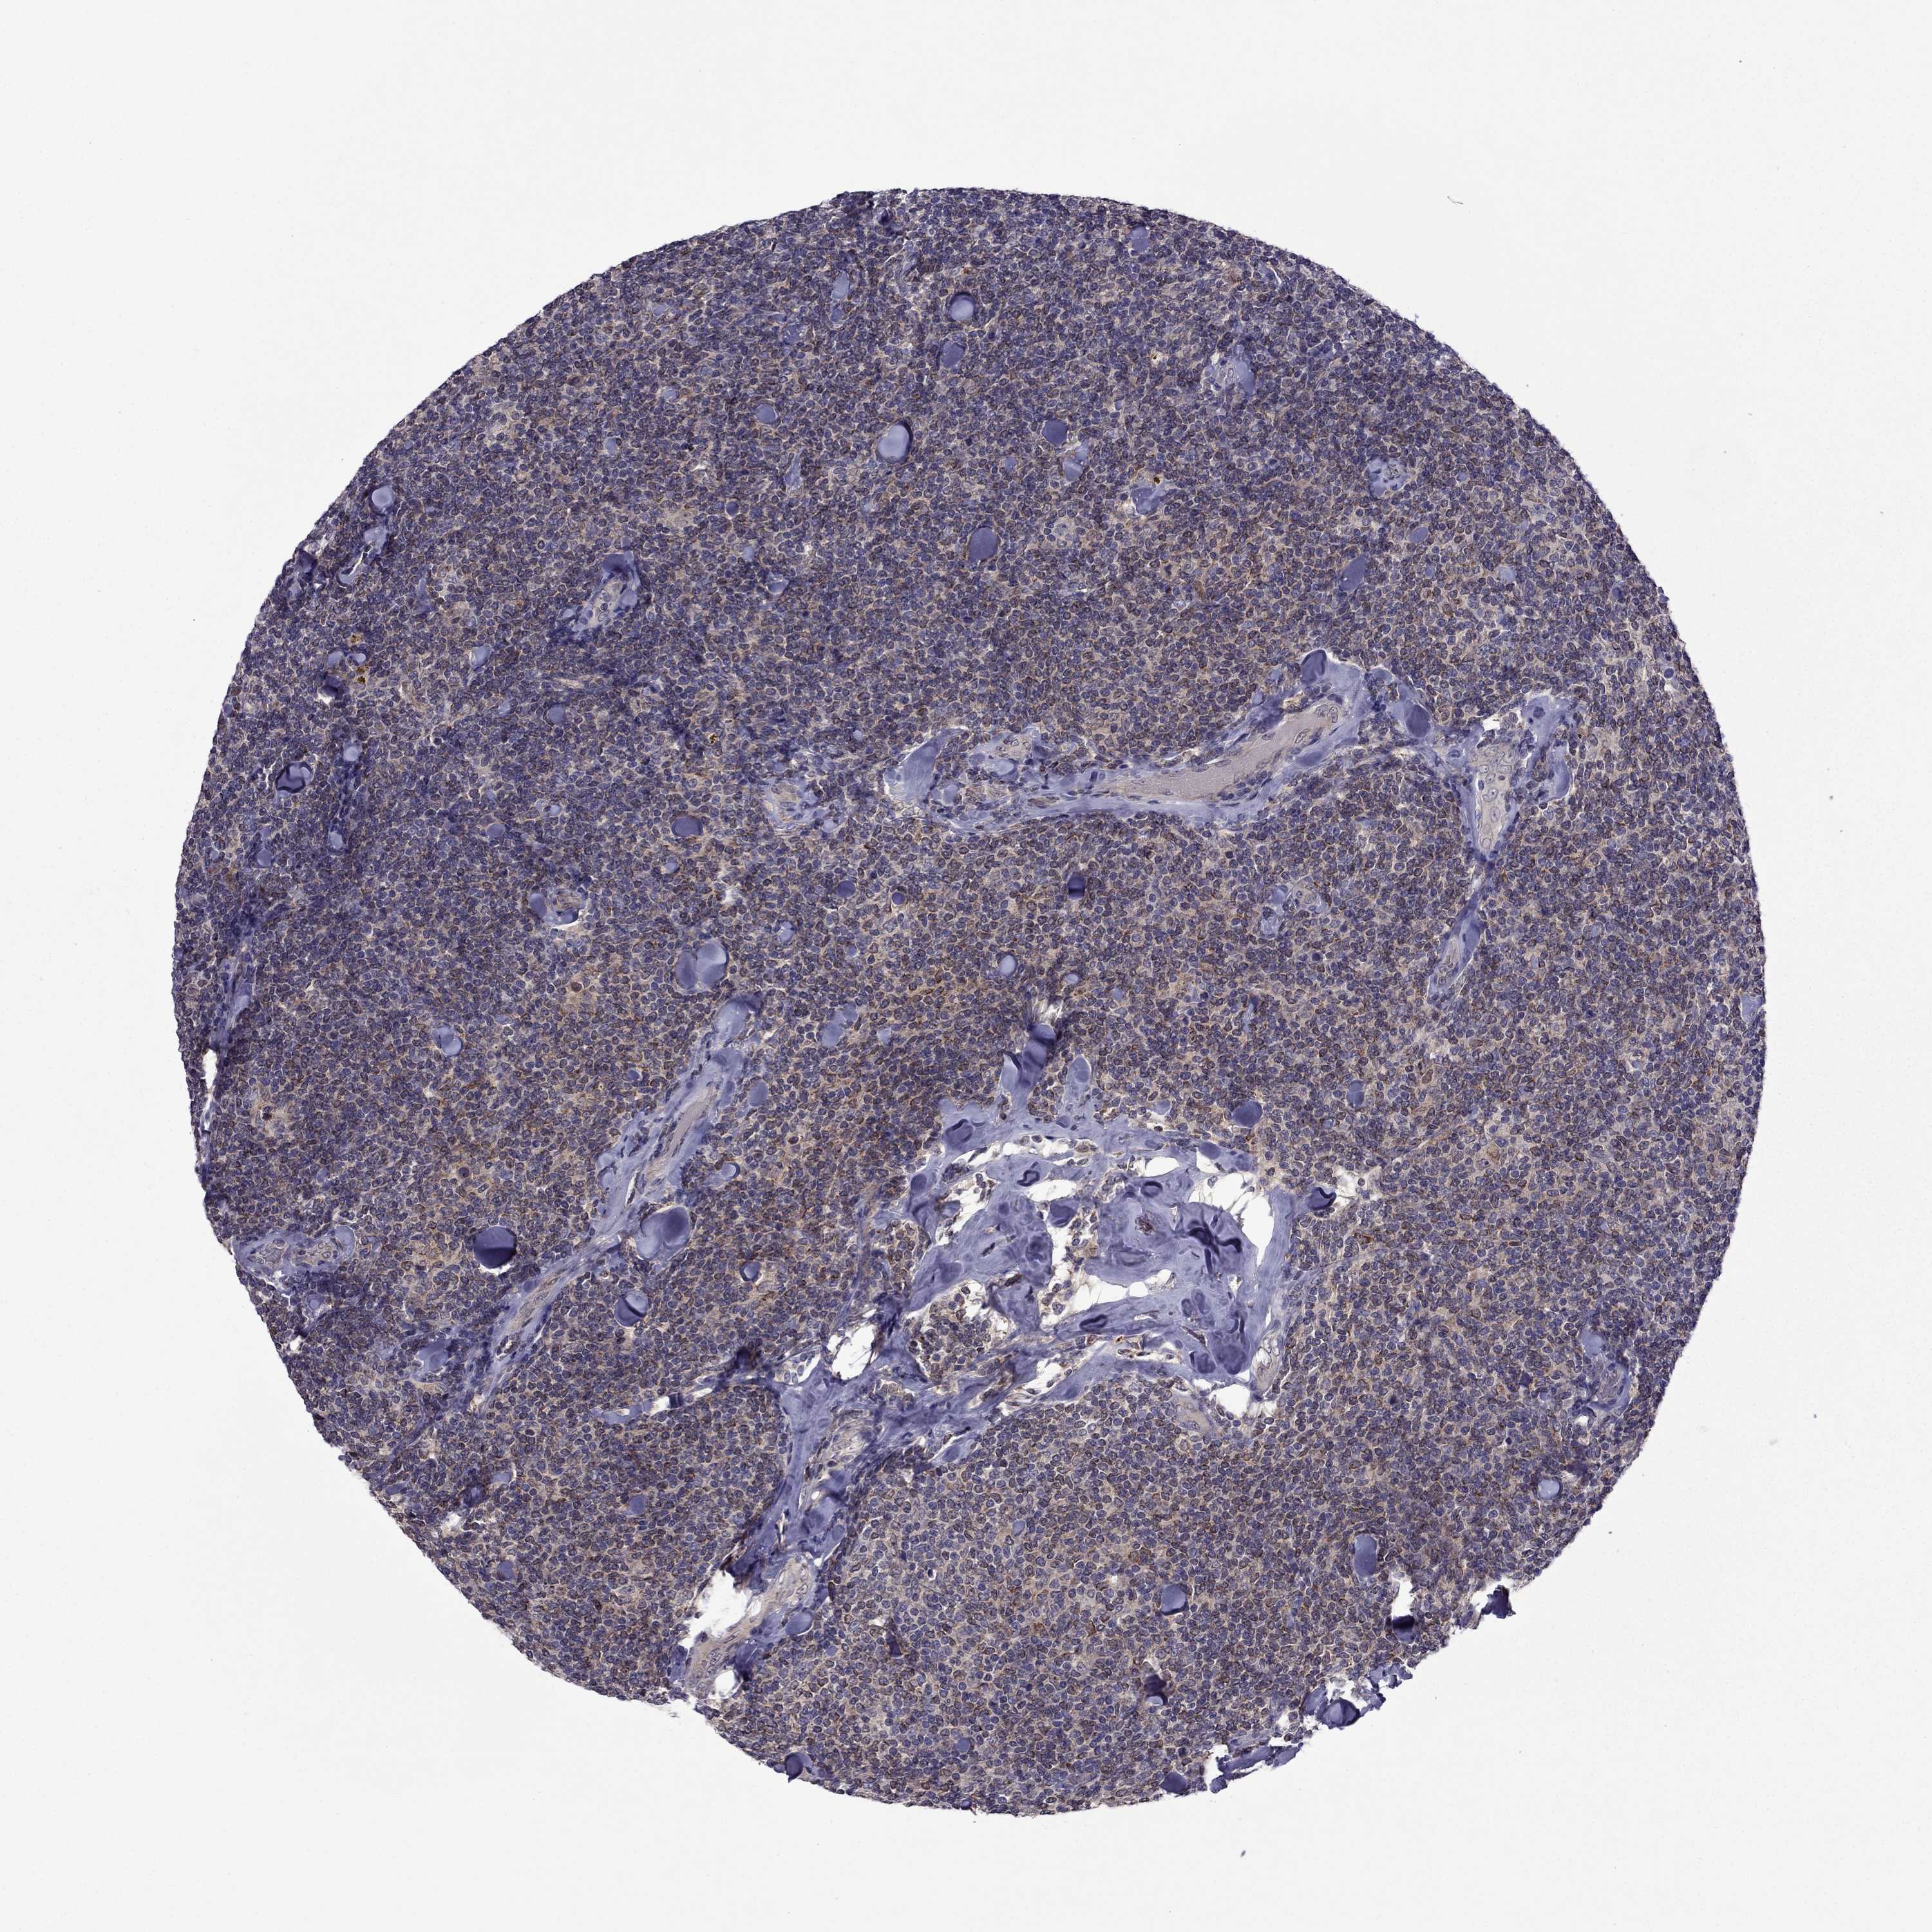

LYMPHOMA - Protein expressioni

A mouse-over function shows sample information and annotation data. Click on an image to view it in a full screen mode. Samples can be filtered based on level of antibody staining by selecting one or several of the following categories: high, medium, low and not detected. The assay and annotation is described here.

Antibody staining in the annotated cell types in the current human tissue is reported as not detected, low, medium, or high, based on conventional immunohistochemistry profiling in selected tissues. This score is based on the combination of the staining intensity and fraction of stained cells.

Each image is clickable and will lead to virtual microscopy that enables deeper exploration of all samples and also displays staining intensity scores, fraction scores and subcellular localization as well as patient and tissue information for each sample.

Antibody CAB008909

Staining

High

Medium

Low

Not detected

Intensity

Strong

Moderate

Weak

Negative

Quantity

>75%

75%-25%

<25%

None

Location

Nuclear

Cytoplasmic/membranous

Cytoplasmic/membranous,nuclear

Malignant lymphoma, non-Hodgkin's type, High grade